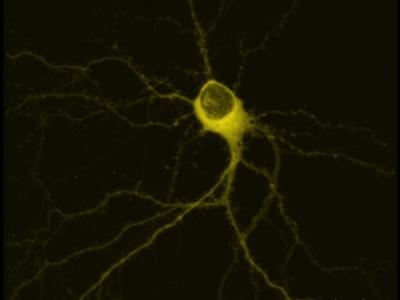

科学家发现新生脑细胞能清除旧记忆

海马神经元 日本科学家13日在《细胞》杂志上发表研究文章称,新生脑细胞能破...